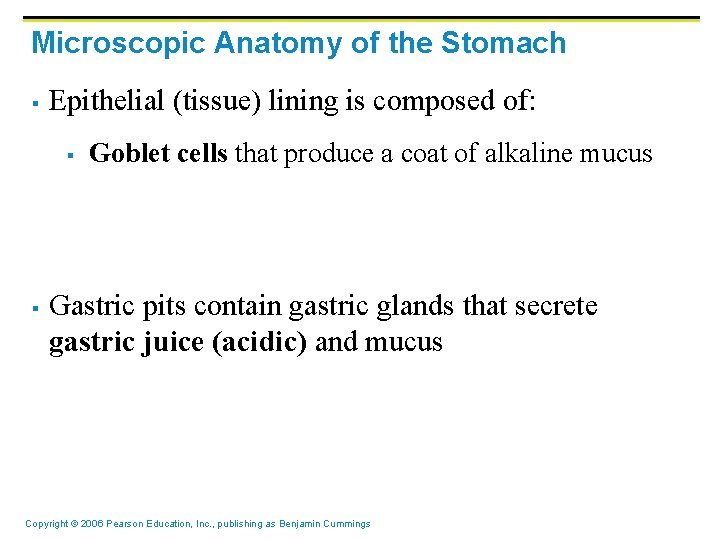

Microscopic Anatomy of the Stomach § Epithelial (tissue) lining is composed of: § § Goblet cells that produce a coat of alkaline mucus Gastric pits contain gastric glands that secrete gastric juice (acidic) and mucus Copyright © 2006 Pearson Education, Inc. , publishing as Benjamin Cummings